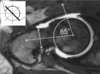

Mencione que método para calcular inestabilidad radio cubital es el mostrado a continuación:

Método de Mino o de la línea radiocubital